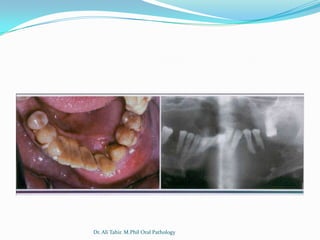

Radiographic

 Compound

 Unilocular, containing multiple radiopaque structures

resembling miniature teeth

 May contain 2-3 or upto 20-30 tooth like structures

 Complex:

 Unilocular,usually small but may grow upto 10cm

 Solid radiopaque mass

 Surrounded by thin zone of radiolucency

 Cortication

 Usually associated with

an unerupted tooth

 A developing odontoma

may be radiolucent

 Radiographic findings

are usually diagnostic